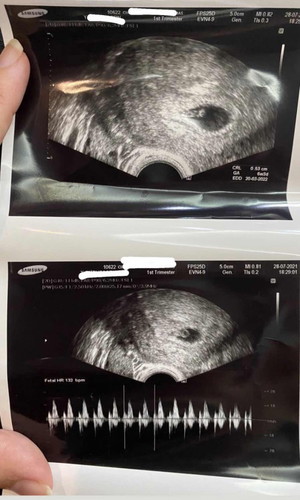

อันนี้ซาวด์ช่องคลอดหรือซาวด์หน้าท้องคะ เห็นน้องเร็วจัง

ซาวหน้าท้องเห็นรางๆ